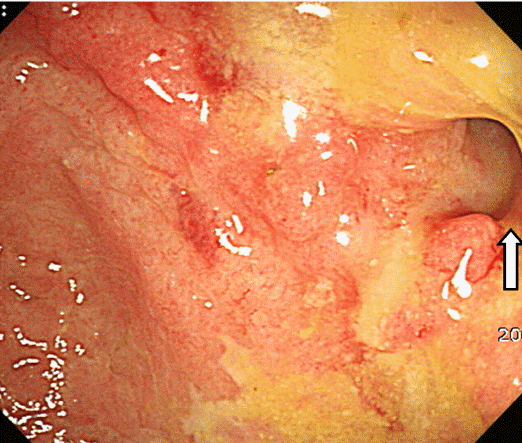

내시경 및 위장관 영상 소견: S상결장 검사에서 직장 S상결장 접합부위 협착 및 1시 방향으로 큰 궤양과 황갈색 삼출물 소견(Fig. 2)이 보였다. 바륨검사에서는 협착부 위로 커다란 궤양이 보였으며, 협착부 아래로는 허혈성 장염에서 보이는 엄지손가락으로 눌린 듯한 모양(thumb-printing)이 보였다(Fig. 3). 그러나 크론병을 시사하는 선상 궤양, 장간막면의 단축 등의 소견은 없었다.

Figure 2.

Colonoscopy shows a large ulcer and stricture at the rectosigmoid junction.